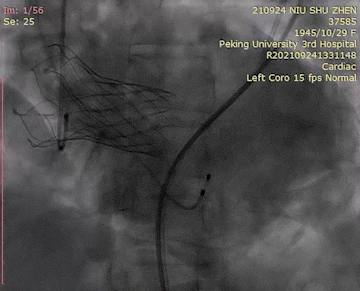

主动脉根部造影

瓣膜定位

极限回收前造影

瓣膜释放

无瓣周漏,瓣环锚定良好